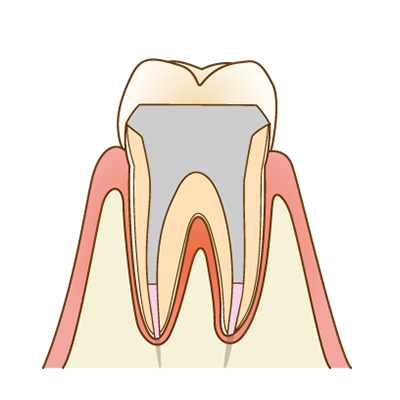

土台(コア)の作製

根管治療後は、被せ物を支えるための土台(コア)を作製します。歯の状態に合わせて、歯に負担の少ない方法を選択します。

補綴修復(被せ物)

最後に、歯を守るための被せ物(クラウン)を装着します。被せ物は、見た目だけでなく、歯との適合精度が非常に重要です。マイクロスコープを用いて適合を確認し、細菌が入り込みにくい状態を目指します。